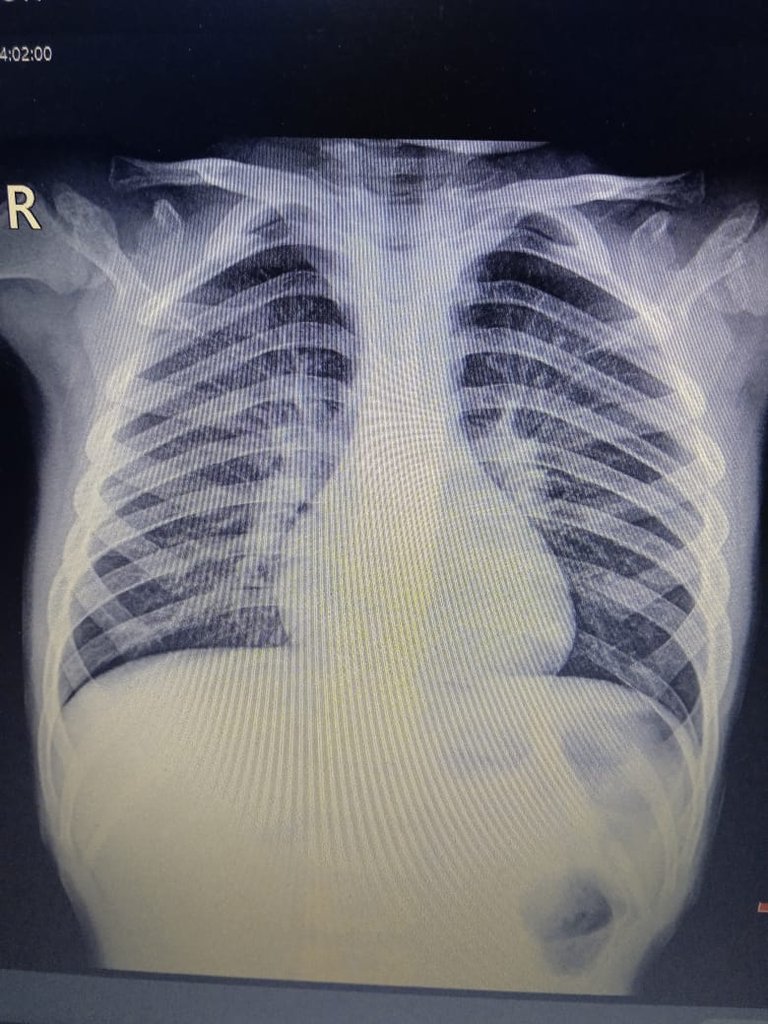

Su consejo fue una orden llena de esperanza: Vaya al hospital mañana, repita los exámenes y búsqueme. Les haremos placas de tórax. Esa intervención no fue casual; fue el cable a tierra que necesitaba para no desconectarme por completo.

Los resultados definitivos de algunos exámenes tardarán, pero por ahora tenemos un diagnóstico claro y un tratamiento que seguir. La neumonía bilateral en mis dos niños pequeños y la bronquitis en mi hijo mayor son condiciones serias, pero por fin tienen un nombre y un camino a seguir.

Her advice was a hopeful command: Go to the hospital tomorrow, repeat the tests, and find me. We'll take chest X-rays. That intervention wasn't a coincidence; it was the anchor I needed to keep from completely disconnecting.

The final results of some tests will take time, but for now we have a clear diagnosis and a treatment plan. Bilateral pneumonia in my two young children and bronchitis in my older son are serious conditions, but they finally have a name and a path forward.